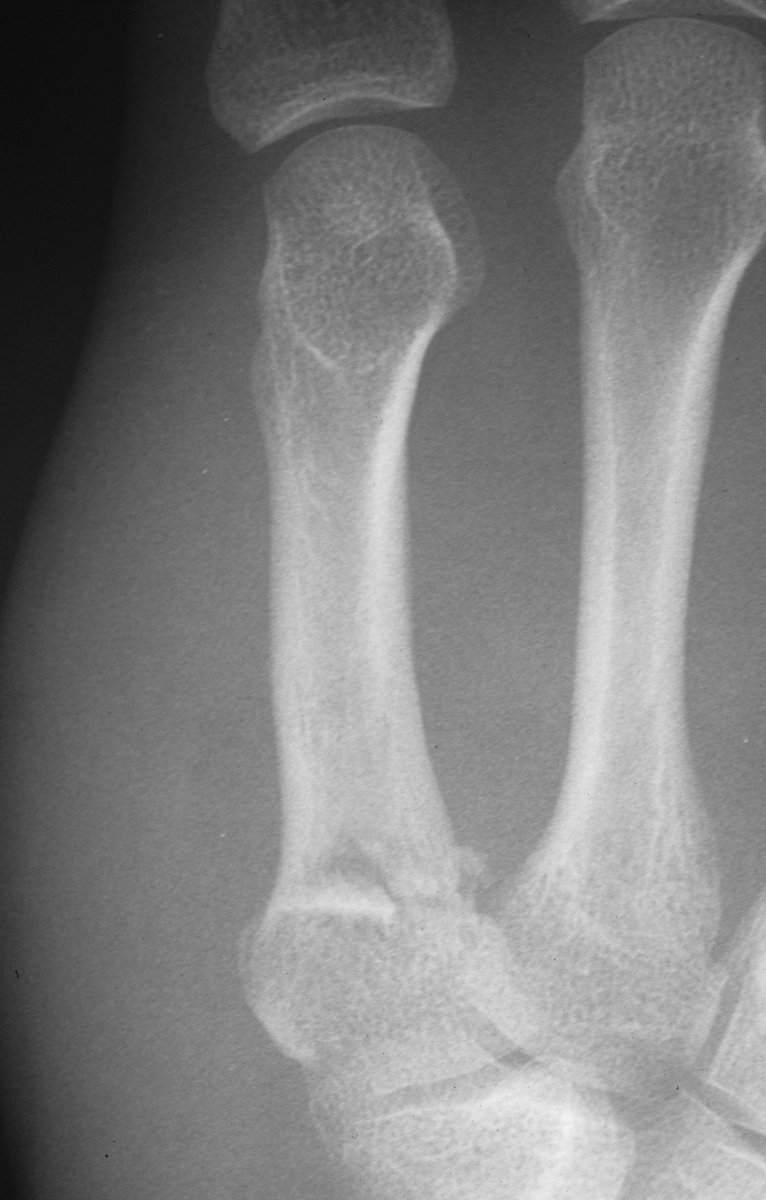

Case 4

Rotated unstable spiral oblique proximal phalanx

fracture. |

| Reduction and fixation. |

| Appearance at four

weeks. |

| Late result. |